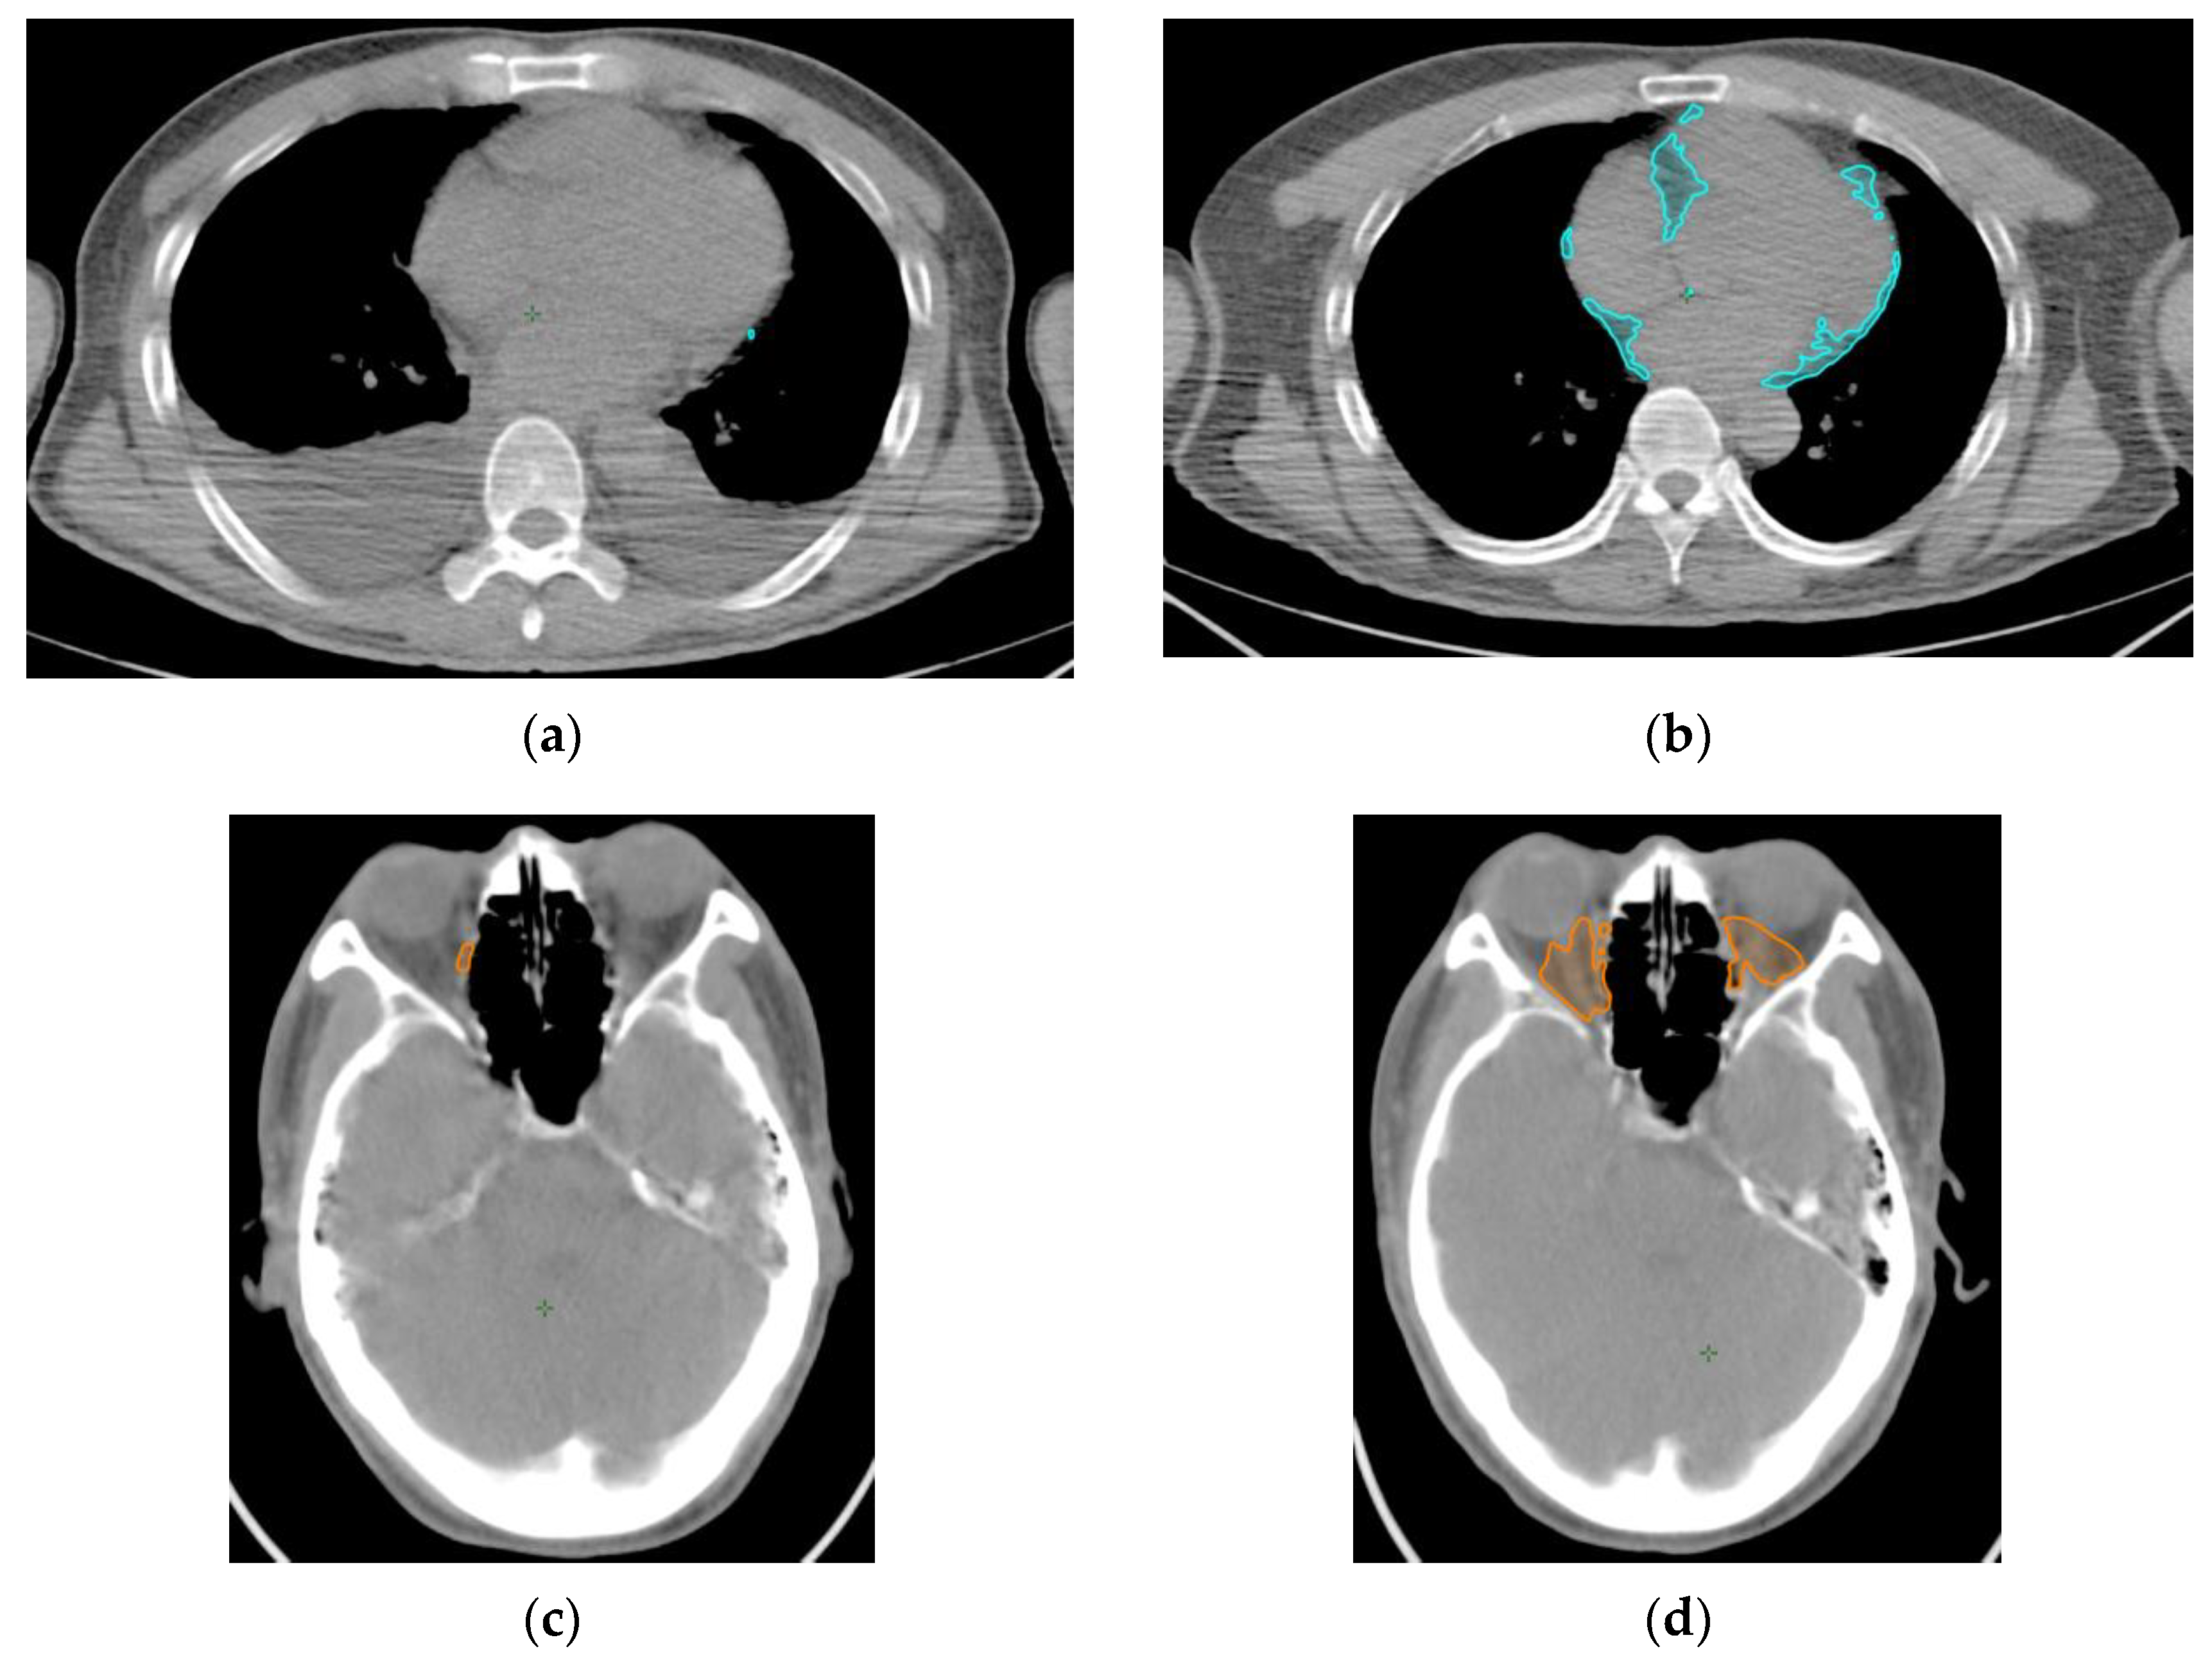

4. Materials and Methods